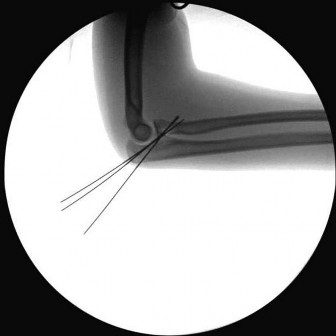

A 45-year-old male sustains the injury pattern depicted in the provided image. During surgical reconstruction of the lateral collateral ligament complex, identifying the correct isometric origin of the lateral ulnar collateral ligament (LUCL) on the distal humerus is critical. Where is this point located?

Options:

Correct Answer: At the center of the axis of rotation of the capitellum

Explanation:

The isometric point for the LUCL origin on the humerus is the center of the axis of rotation of the capitellum. Placing a graft or suture anchor at this specific geometric location ensures that the reconstructed ligament maintains relatively constant tension throughout the elbow's entire arc of flexion and extension.